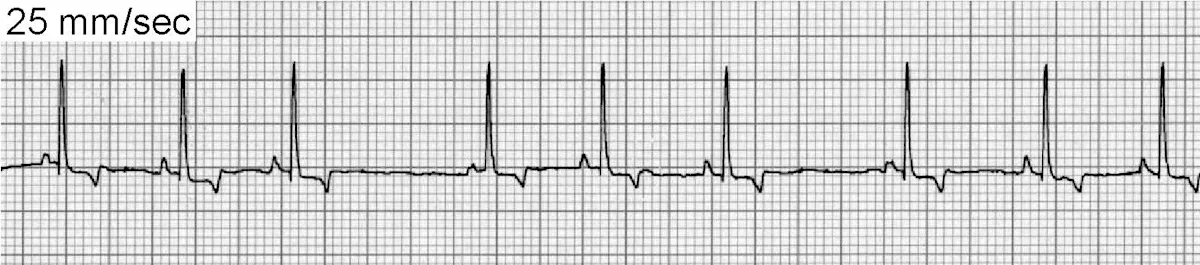

Ventricular Premature Complexes

VPCs (Figure 5) can be associated with significant inflammatory, structural, toxic, infiltrative, traumatic, or ischemic heart disease. VPCs are also common in patients with noncardiac disease (eg, gastric dilatation-volvulus [GDV], splenic disease/surgery, hyperthyroidism, sepsis, anemia, hypoxia, myocarditis/infectious disease, coagulopathies). Patients with elevated sympathetic tone from extreme excitement or pain may also display VPCs, as well as drug therapy with digoxin, anesthetics (especially short-acting thiobarbiturates), and catecholamines.

ECG of ventricular premature complexes

ECG of ventricular escape beats

VPCs generally occur <1 R-R interval from the preceding sinus beat (vs ventricular escape beats [Figure 5B] that generally occur >2 R-R intervals from the preceding sinus beat) and are not associated with preceding P waves. Care must be taken to exclude these arrhythmias from sinus rhythm with chamber enlargement patterns or sinus rhythm with conduction disturbances.

The decision to treat VPCs can be difficult. Frequent and multiform VPCs in the presence of underlying heart disease, especially with clinical signs, will necessitate treatment. Infrequent, uniform VPCs without clinical signs or heart disease uncommonly require treatment. Treatment for VPCs secondary to underlying metabolic disease is usually not indicated and therapy should instead be aimed at correcting the underlying condition.